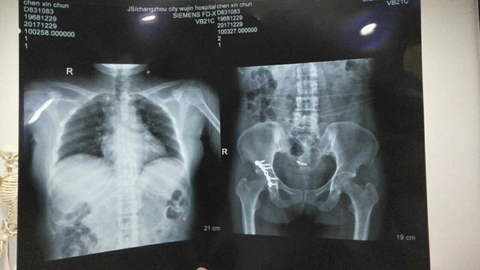

我叫陈新春,女,1968年3月出生,小学文化程度,江苏省盐城市射阳县人。2017年11月3日,在江苏省常州市新北区文化广场工地,八号楼二楼清理施工垃圾。因安全措施不到位,从6米高空施工洞坠入,造成颈椎骨折,脊柱骨折,腰椎L1一6横突骨折,腰椎右侧横突骨折,右侧髋臼,股骨头骨折装钢板,盆骨右侧L1一5骨折,左侧L1一5骨折,双侧耻骨折,左侧髋臼可疑骨折,腰椎至骨盆除左侧髋臼可疑骨折,全部骨折,外阴跌撕,胸椎骨折,内骨粉质性骨折,内骨右侧横突L1一4骨折,内骨左侧3一7两处骨折,右侧肋骨L1一10骨折,右侧肋骨后缘3一7两处骨折,左侧肋骨1.2.3.5.6.7.10骨折,后缘肩往下1一4两处骨折,左肩袖损伤肌健骨折;左冈上肌损伤,左肱骨因血液不流通,左肱骨长一个小圆形囊肿,腹部闭合性损伤,全身多处软组织损伤;双侧微量气胸,肝挫伤出血,脾挫伤出血,左肾挫伤出血,右肾上泉挫伤伴血肿,右肺上叶及两肺下叶挫伤出血,内腹部都挫伤出血。

这里所提供的几张片子拍出的颈椎骨折,腰椎横突骨,脊柱骨折,左侧盆骨骨折,内骨粉质性骨折,内骨左侧3一7两处骨折胸椎骨折,报告单都没有。报告单上有50根骨折包括两处有的,只出三分之一的骨折。常州市武进人民医院涉嫌隐瞒我的伤情,进手术室开刀涉嫌隐瞒了主要骨折的片子,去要片子不给;补出院小结,补两次,颈椎骨折,腰椎骨折,胸椎骨折,内骨粉质性骨折还不肯补。